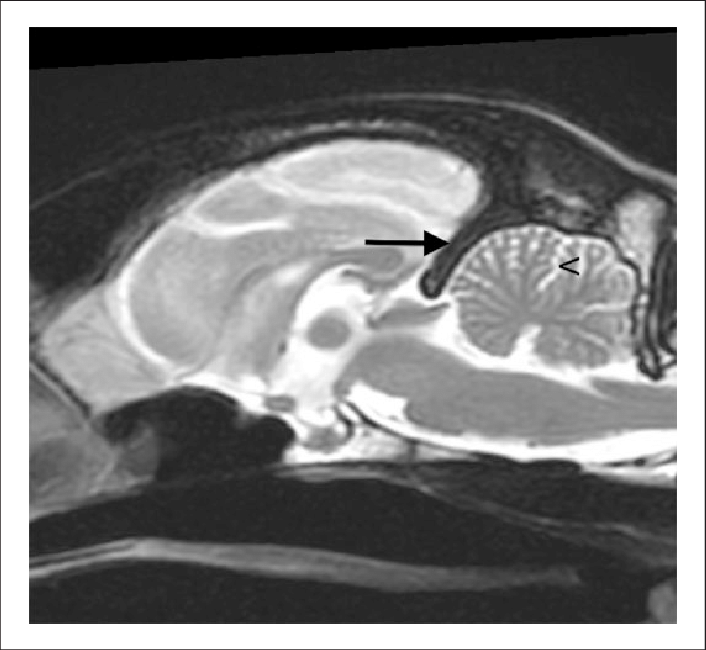

What structure is the black area pointing to?

Osseous tentorum cerebrii

What structure is the asterik in?

Dorsal pouch of the distal interphangeal joint